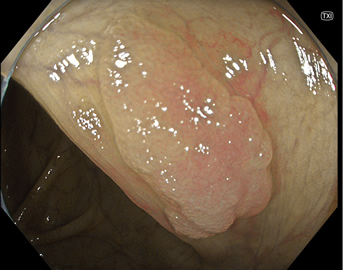

特に、下のような「Ub型(全く凸凹の無い完全に平坦な病変)」は、以前は「ほとんど見つからなかった」のが、TXIを使うようになってから「日常的に」見つかるようになりました。

通常観察 TXIモード

青い色素は追加していません![]()